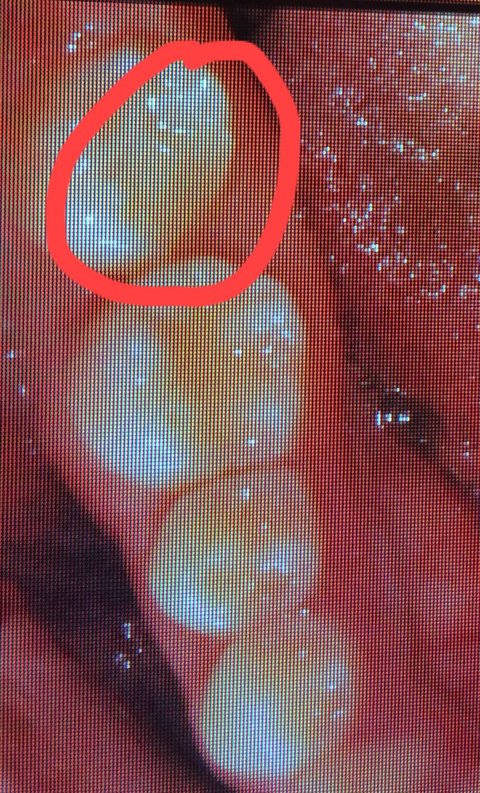

이렇게 티가 나게 깨져있는데 제가 치과 바로 가기 전에도 양치하고 치 실질 했을 때도 이러지 않았는데 저 어금니 안쪽에 브래킷 장착했었고요 아무래도 브래킷 제거하면서 깨진 거 같은 느낌이 들더라고요 그래서 오늘 충치 검사할 겸 다른 치과 갔는데 저거 깨진 거는 치아 때운 게 깨진 게 아니라 제 치아가 깨진 거고 32만 원 주고 부분만 씌우라고 했던 왼쪽 아래 끝 어금니는 겉에 충치는 있지만 씌울 필요는 없고 주기적으로 검사는 하되 더 심해지면 씌워야 한다고 하더라고요 바로 교정치과 전화해서 어제 마지막 상담한 실정한테 이때 운 게 깨진 게 아니라 제 치아가 깨졌는데 뭔 말이냐니까 깨졌다는 말은 한 적이 없고 충치가 심해서 씌우라는 거였다고 그래서 내가 방금 다른 치과를 다녀왔는데 깨지기만 했지충치는 아예 없다고 하고 그쪽에서 치료하라는 반대편 치아는 치료할 필요 없다고 했다 장치 떼면서 그쪽에서 깨트려놓고 왜 나한테 돈 내라고 하냐 했더니 치과에 오라고 해서 가겠다고 하고 혹시나 사진 조작할까 봐 처음 사진 보고 어느 쪽 치아든 육안으로 깨진 치아가 있느냐라고 했더니 없다고 하더라고요 치과에 가서 실장을 만났는데 원래 오른쪽 맨 끝 치아는 깨져있었다며 말을 또 바꾸길래 아까없다하지않았냐니까 치아 겉 쪽만 확인했지 안쪽을 확인 못 했다 하길래 내 치아가 처음부터 깨져있었으면 지금 사진 찍어 비교했을 때 같아야 하는 건데 내가 모르고 있었다면 지금 사진 찍어서 비교를 하자니까 눈에 띄게 깨져있더라고요

이게 지금 사진인데 어떻게 같을 수 있답니까

누가 봐도 티 나게 깨져있는데 ..

이게 지금 같아 보이느냐 원래 깨져있었으면 장치